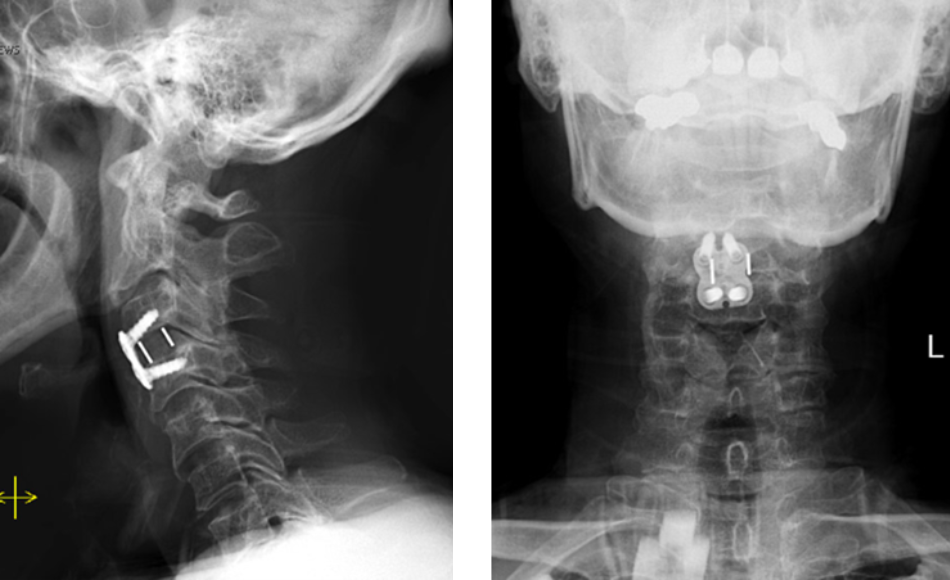

Spine:

Central Cord Syndrome

Author: Yusef Imani M.D., F.A.A.N.S., Read More!